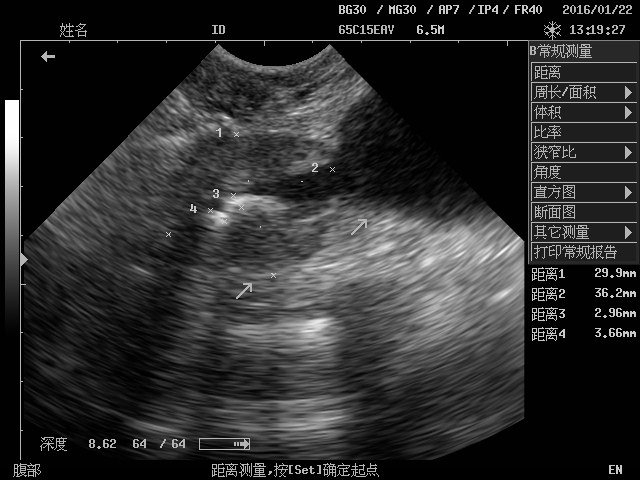

贵宾犬,昵称:孜孜,8岁,雄性。

2016122日,主人携带孜孜因尿淋漓,4天不吃,从其他医院转诊至我院,B超、血常规、生化检查后诊断为膀胱结石,尿道结石,前列腺增生,肝功能损伤,肾后性氮质血症。与主人沟通后,尝试导尿管推结石入膀胱,导尿后输液2小时,任然不能自主排尿。决定B超引导留置导尿管推结石入膀胱,发现结石停留在膀胱颈前列腺处尿道内,放置导尿管,2天后手术治疗。2016124日,采用呼吸麻醉手术取出膀胱和尿道内结石,术后继续放置导尿管3天,常规输液消炎、调整身体。导尿管取出后孜孜可以顺畅的小便了,食欲正常了,精神也好了,主人是新华医院的医生几次打电话致谢我们,谢谢他对我们的认可。